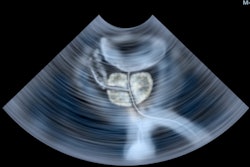

The aim of the MRI-guided transurethral ultrasound therapy system treatment report (TULSA-Pro) is to ablate the prostate tissue of patients with localized, organ-confined cancer. Figure courtesy of Prof. Afshin Gangi.

TULSA, or transurethral ultrasound ablation, uses heat to target and destroy cancerous prostate tissue. It combines real-time MRI with robotically-driven directional thermal ultrasound and closed-loop temperature feedback control software, delivering transurethral prostate tissue ablation of whole-gland or partial prostate tissue, he explained.

"What I like about this technique is that the source is the center of the prostate," Gangi said. "TULSA works with ten sources of emitters, or torch lighters that rotate robotically throughout the prostate. It's a flame that shoots from the base to the periphery."

Technically, it is necessary to place the 10 emitters and decide where to start, either left or right. Radiologists can do that easily as they control thermometry. The probe is placed in the urethra; once the bypass is done, energy can be delivered automatically. The patient can be discharged on the next day, Gangi added.